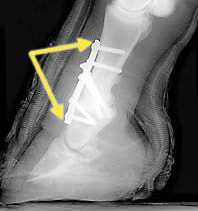

関節固定術

手首や足首でも痛みが強いときに固定術を行うことがあります。しかし、痛みはとれても関節が動かなくなってしまうために、かえって日常生活において不便になることもあります。